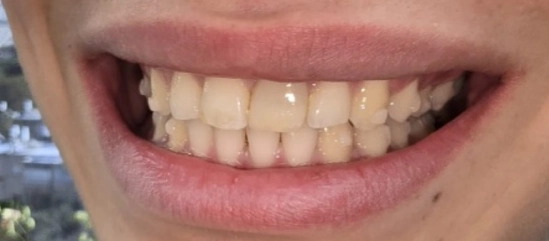

תמונות לפני ואחרי טיפול

אחרי

בסיום הטיפול התקבלה תוצאה אסתטית ותפקודית ברמה גבוהה מאוד. יחסי הסגר שופרו, הצפיפות נפתרה, הקשתות יושרו, והמראה של האזור הקדמי השתנה באופן משמעותי. מעבר ליישור השיניים, הטיפול הצליח להתמודד עם מצב מורכב של שן קדמית לאחר חבלה, תוך שמירה על זהירות ביולוגית גבוהה ותכנון זהיר של כל שלב. זהו מקרה שממחיש כיצד אורתודונטיה מותאמת אישית איננה רק בחירה במכשור מסוים, אלא היכולת לתכנן את סדר הפעולות הנכון, לשלוט בתנועת שיניים באופן סלקטיבי, להתחשב במגבלות הביולוגיות של כל שן, ולהוביל לתוצאה אסתטית מצוינת גם כאשר נקודת הפתיחה מורכבת במיוחד.